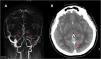

ConclusionesEn nuestra cohorte, la TVC afectó con mayor frecuencia a mujeres jóvenes, y ocurrió en pacientes con al menos un factor de riesgo para TVC. La presencia de edema en la tomografía computarizada y el tratamiento con corticosteroides asociaron un peor pronóstico a corto plazo. Se observó un buen pronóstico a largo plazo en términos de mortalidad, recurrencia y sangrado.

ConclusionsIn our cohort, CVT predominantly affected young women with at least one risk factor for its development. The presence of edema on CT and corticosteroid treatment were associated with a poor short-term prognosis. However, we observed a favorable long-term prognosis in terms of mortality, recurrence, and bleeding.